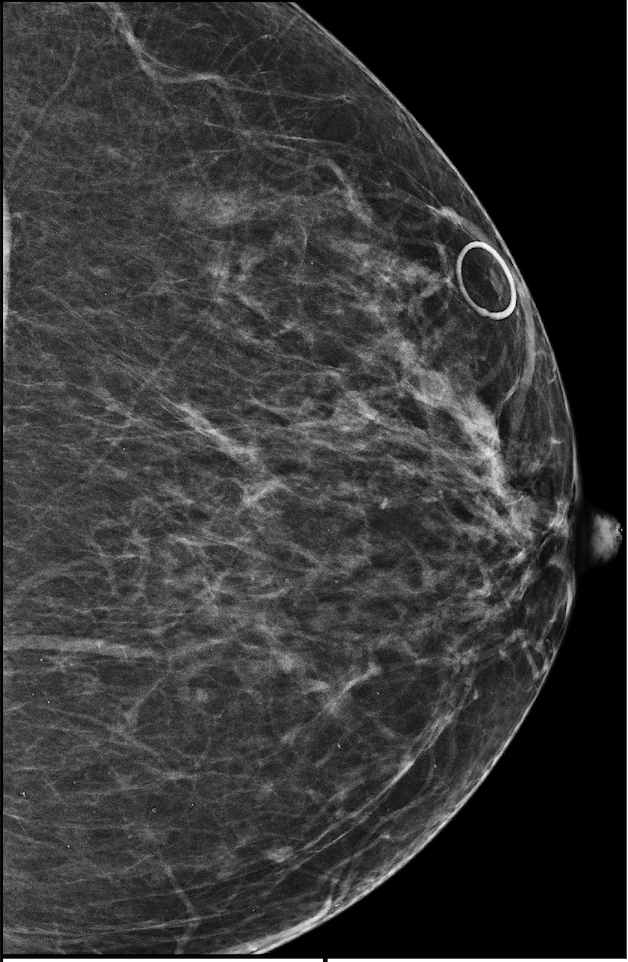

In addition, we observe that GMIC is able to provide meaningful localization when the lesions are hardly visible to radiologists in the image. In Figure 8, we illustrate a mammographically occult mammogram of a 59-year old patient with no family history of breast cancer and dense breasts. There is an asymmetry in the left lateral breast posterior depth which appears stable compared to prior mammograms and was determined to be benign by the reading radiologist. However, the saliency map of malignant findings successfully identifies the malignant lesion on the screening mammogram. Same day screening ultrasound (sagittal image) demonstrated a 1.2 cm irregular mass; ultrasound biopsy yielded moderate grade invasive ductal carcinoma.